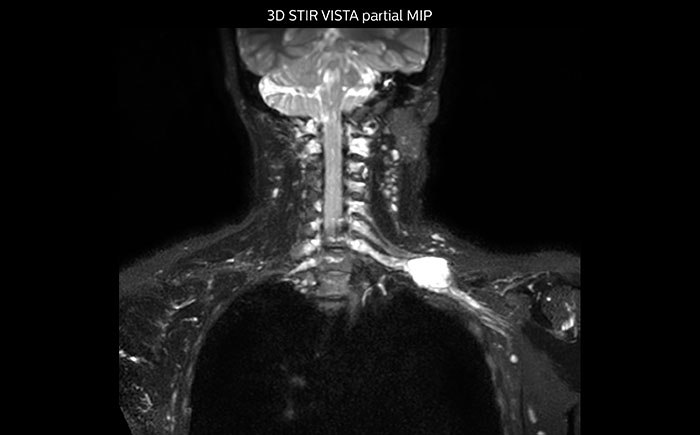

MR neurography of nerve sheath lesion

This patient is a 43-year-old female with a left supraclavicular nerve sheath tumor. The lesion is well visualized on the STIR VISTA images and on the MR neurography using DWIBS. The exam was performed on Prodiva 1.5T.

MR neurography using DWIBS inverted, full MIP

Acq voxel size 1.2 x 1.3 x 2.4 mm, Recon voxel size 0.7 x 0.7 x 1.2 mm, dS SENSE factor 2, scan time 5:46 min.